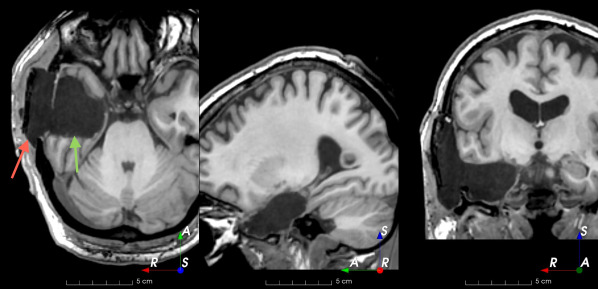

Refer to caption

(a)

(b)

(c)

(d)

(e)

(f)

(g)

(h)

Figure 6: Examples of challenging images for cavity segmentation. (a) Small frontal lesionectomy surrounded by hypointense white matter (b) Brain shift after contralateral temporal lobectomy (not shown) (c) Small frontal lesionectomy near the Sylvian fissure (d) Lack of boundaries between oedema and resection cavity (e) Possible blood clot within the cavity (f) Brain shift, oedema and resection cavity (g) Arachnoid cyst and resection cavity (h) Cerebellar degeneration. Green annotations represent areas that correspond to resection cavities; red annotations represent areas that do not.